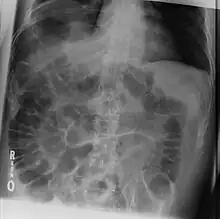

An X-ray image of the intestines, showing coiled loops that are darker on the left and right sides and lighter in the middle

The dark areas on both sides of the intestines indicate that air is present in both sides. This is called "Rigler's sign".